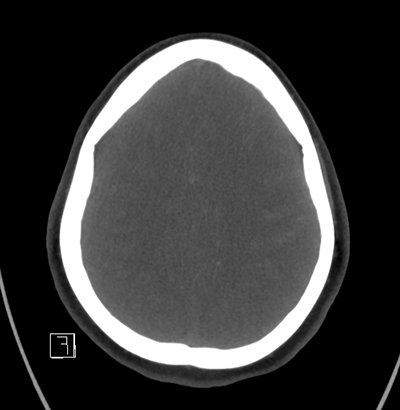

NCHCT

With that in mind, as we look at her neuroimaging, it's subtle, but we can appreciate a faint SAH in the left frontal lobe convexity. Her vessel imaging is unremarkable.